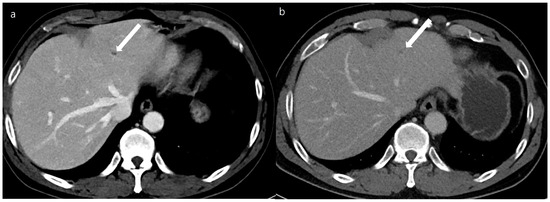

Figure 2. A 65-year-old man with a 0.8 cm sized hepatocellular carcinoma at segment 5 of the liver (arrows). Arterial phase (a), portal phase (b), and delayed phase (c) images of a double low-dose CT using a deep-learning-based contrast-boosting model show a well-enhancing nodule on the arterial phase (a), with washout on the portal phase (b) and the delayed phase (c).